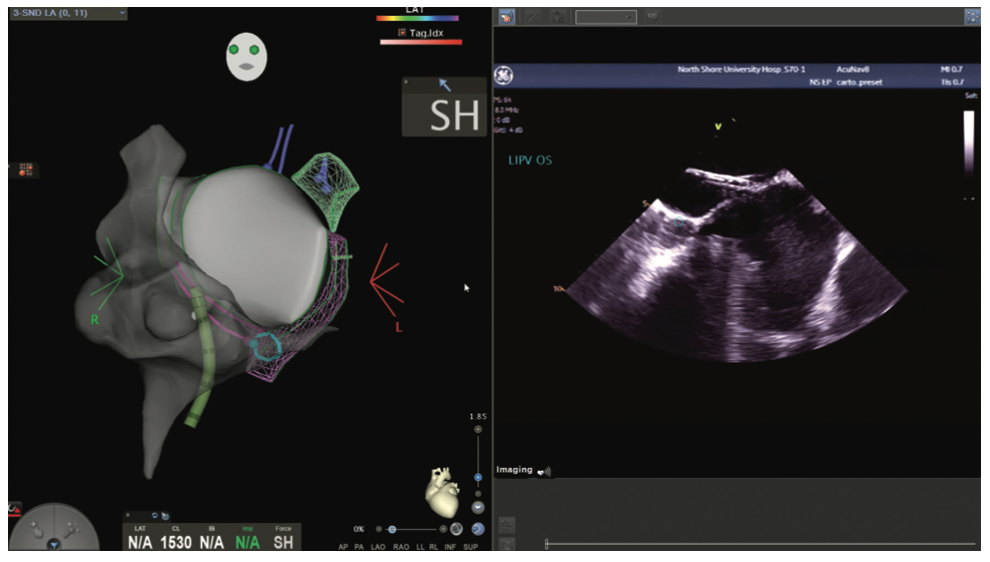

Figures/Videos 1-10 demonstrate the process of navigation from groin access to the heart to create biatrial geometry, localize the esophagus, and gain transseptal access. Many currently practicing electrophysiologists use very little fluoroscopy to map and ablate the left atrium (LA) with the current multielectrode catheters and EAM systems once transseptal access is obtained.

Video 11a and Figure 11b show the voltage map of the LA as well as the pliability of the Pentaray spline catheter to adapt its shape to vessels (a right middle vein) and the endocardium.